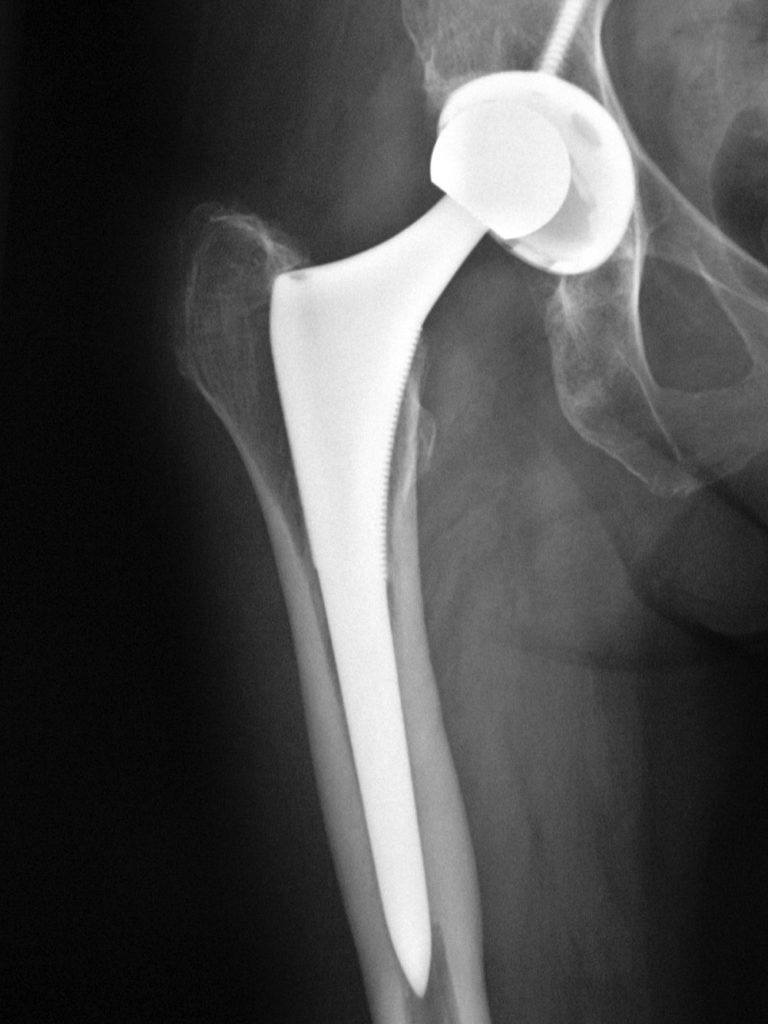

Эндопротезирование тазобедренного сустава: фото и схемы